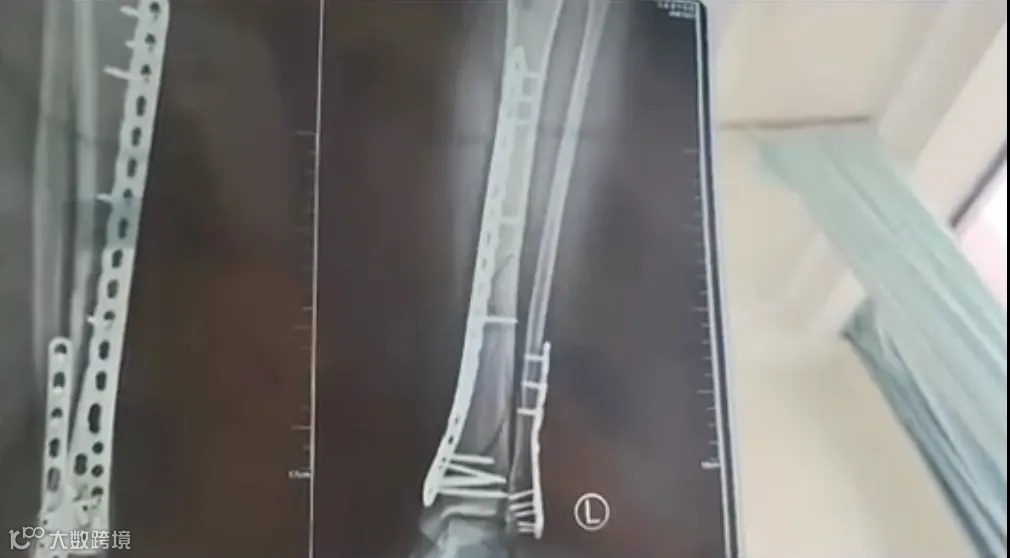

比如说去年6月,甘肃一女子穿7厘米厚底洞洞鞋下楼,崴脚致粉碎性骨折。